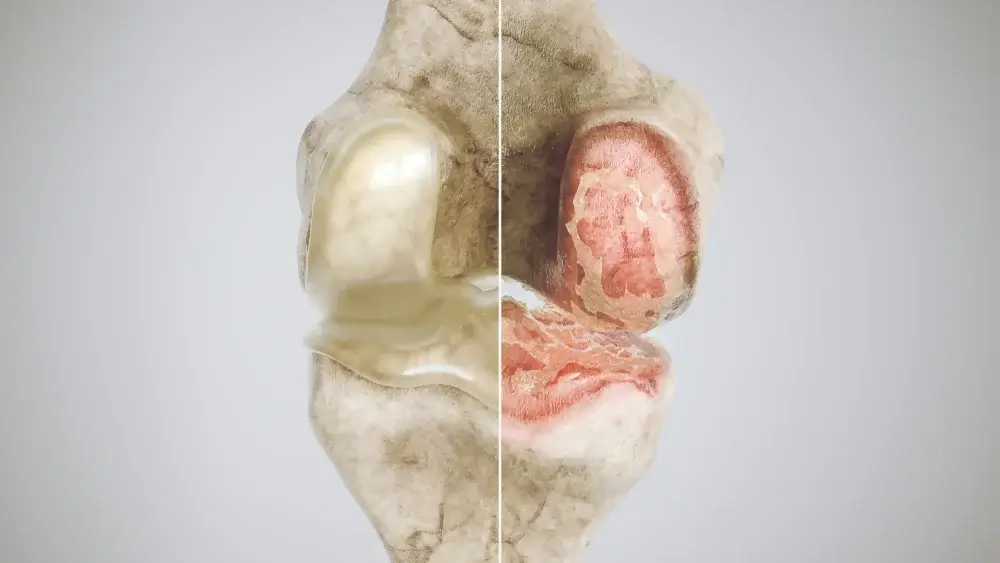

Osteoarthritis:

Osteoarthritis is a common condition that affects the joints. It can be caused by the wear and tear of the cartilage in the joints, which can lead to inflammation and pain.

Osteoarthritis is a degenerative joint disease that affects the bones and cartilage of the joints.

It can be classified into two main types: rheumatoid arthritis and osteoarthritis.

Rheumatoid arthritis is an autoimmune condition in which the body’s immune system attacks its own tissues, including the joints.

Osteoarthritis is a common condition that affects the elderly, but it can also occur in people of any age.

Osteoarthritis can also be caused by rheumatoid arthritis, a type of autoimmune disease. Musculoskeletal conditions, such as osteoporosis, can also lead to osteoarthritis.